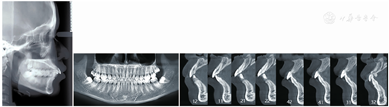

曲面断层片示28、38、48阻生;牙根发育良好,双侧髁突形态结构对称,骨皮质连续;牙槽骨及下颌骨未见明显异常(图2)。CBCT显示:上下前牙牙根靠近唇侧骨皮质,下前牙区骨皮质较薄(图2)。

头颅定位侧位片及头影测量结果示:ANB角与Wits值表明患者为Ⅰ类骨面型;FMA提示患者为低角;U1-NA角、L1-NB角及U1-L1角均表明上下切牙唇倾(表1)。